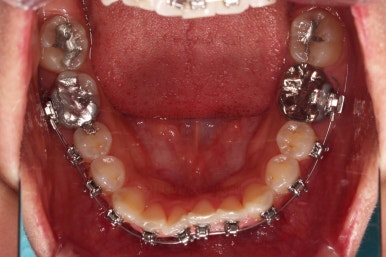

악궁확장 이후에 교정장치를 부착하고 치열을 가지런하게 해줘요.

이번에 사용한 장치는 엠파워 메탈이라고 하는 자가결찰 메탈 장치입니다.

장치 부착 이후의 느낌도 봐주시고요.

치열이 점점 가지런해지죠?

조금만 더 하면 마무리를 할 수 있겠네요.